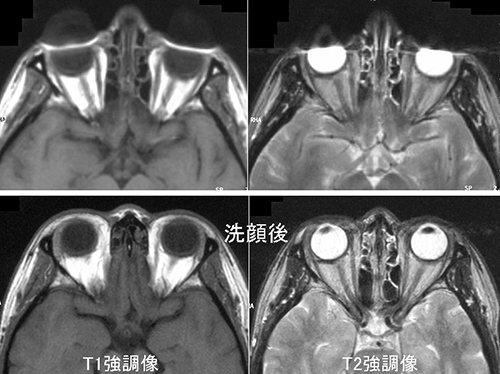

下記に商品説明や配送料・配送方法・注意事項等の説明がございます。MRI認定 43】マジックアングル | ラドライフ。アーチファクト例 - 生理的因子 | 画像診断情報サイト Bayer in。

画像診断 12年1月号 32ー1 特集:MRIアーチファクトの光と影